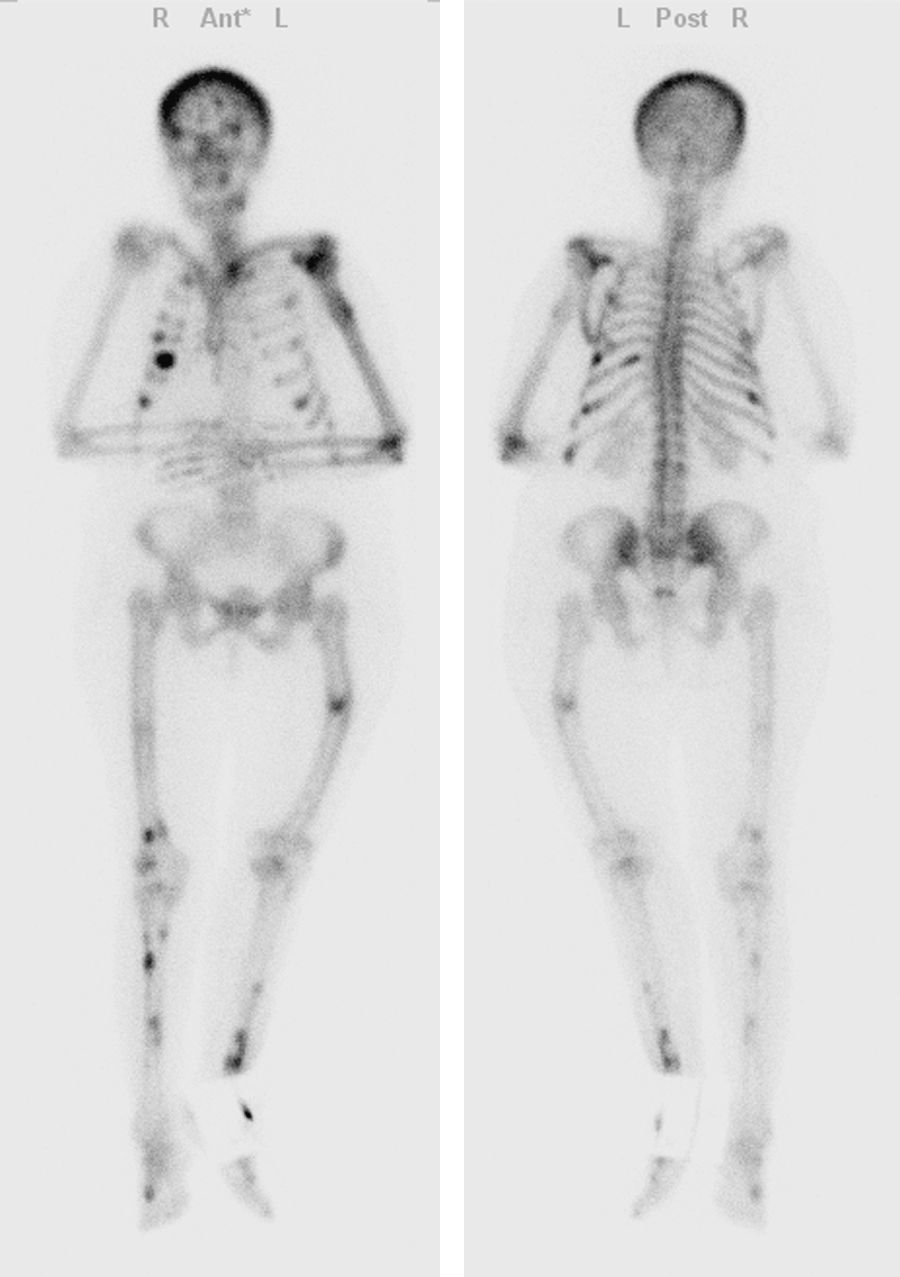

Imaging of multiple brown tumors both in FDG (18F) and 68Ga DOTA-TATE PET/CT studies

Imagen de múltiples tumores pardos tanto en FDG (18F) como en 68Ga DOTA-TATE PET/TAC